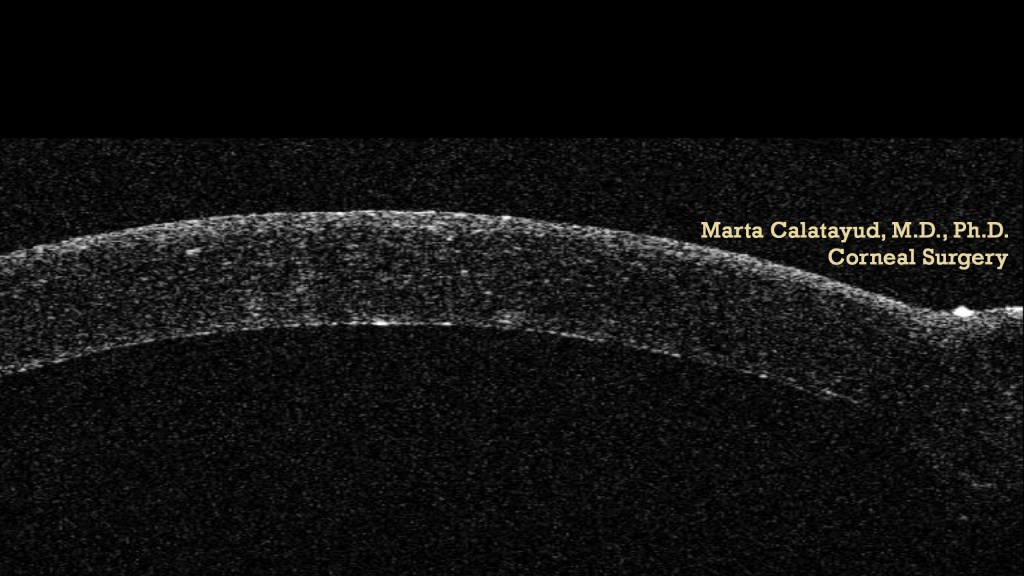

DALK / BIG BUBBLE TECHNIQUE .

martaoft's avatarMarta Calatayud MD PhD